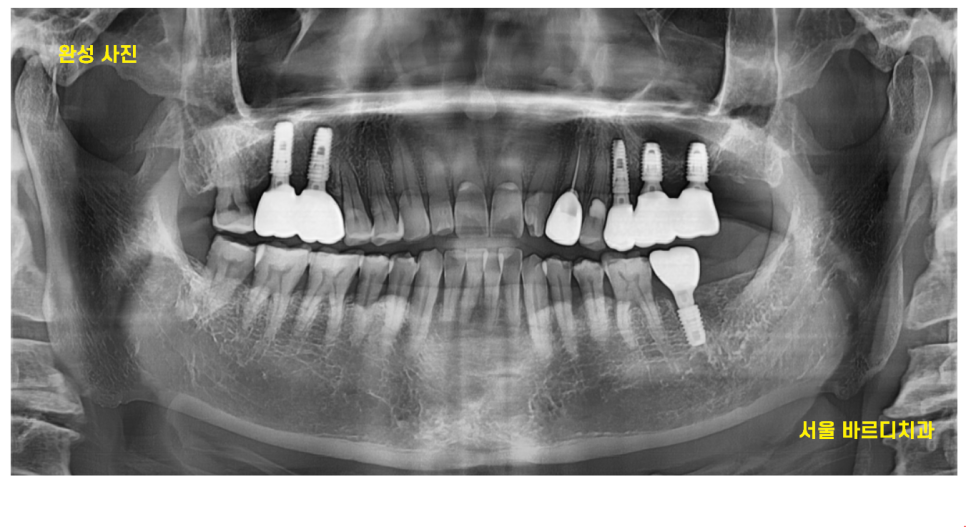

24.07.11

전남 완도에 사시기에

강일동 치과 내원 횟수를 최소한으로

오신 날에 최대한 진료를 많이 진행해드렸는데요.

3월에 수술하고

4개월만에 치료 완료해드렸습니다.